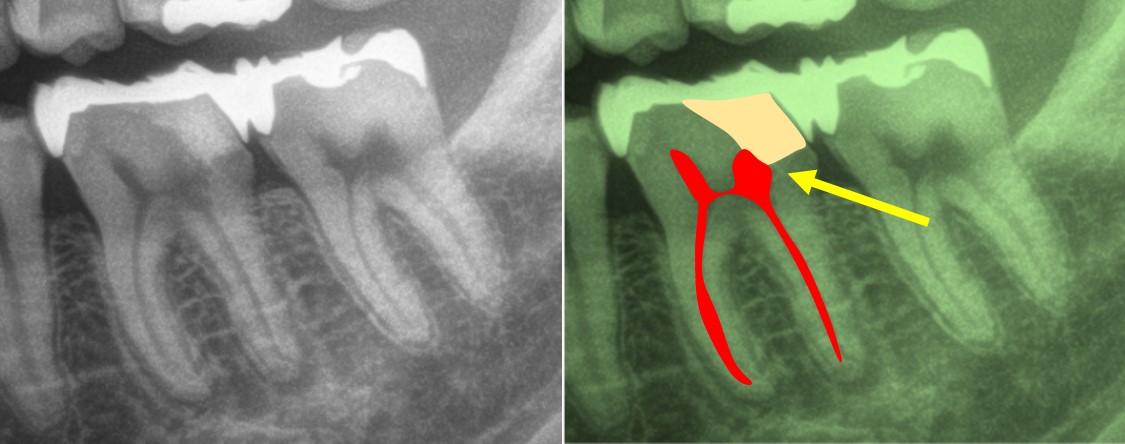

術前のレントゲン所見です。むし歯を取り除き、”セメント”で覆髄(むし歯が神経に近い場合、神経を保護すること)をしていることが読み取れます。

残念ではありますが、このインレー(銀歯)を製作する際、そのような配慮は為されていなかったとのことでした。元は痛みが無かった歯であれば、おそらくその際に感染したと推察されます。

①には、マイクロスコープが必要です。本症例のような複雑な根管を持つ大臼歯では猶更でしょう。